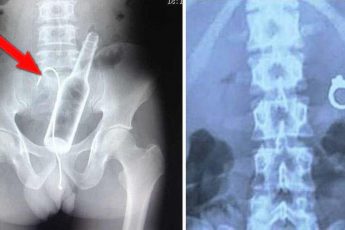

ПАЛЬЦЫ ГИППОКРАТА